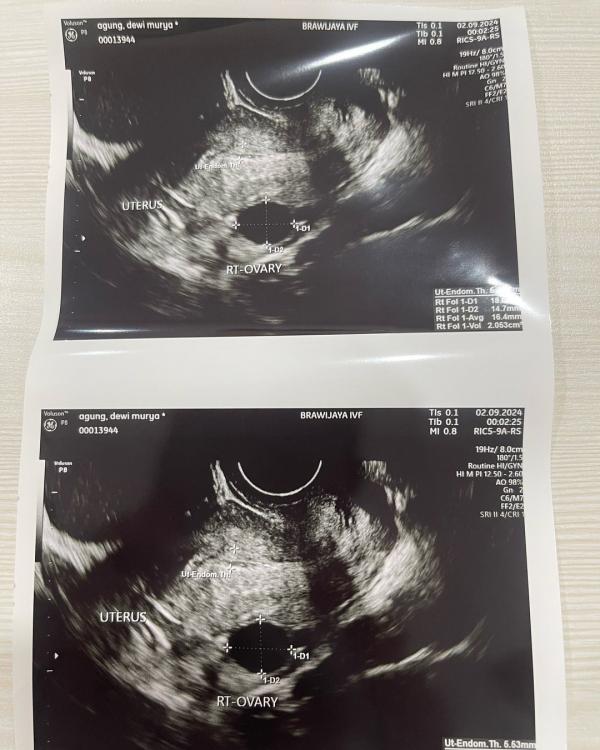

"Yang artinya, sebentar lagi akan masuk masa subur. Tandanya saya gak mandul," kata Dewi Perssik.